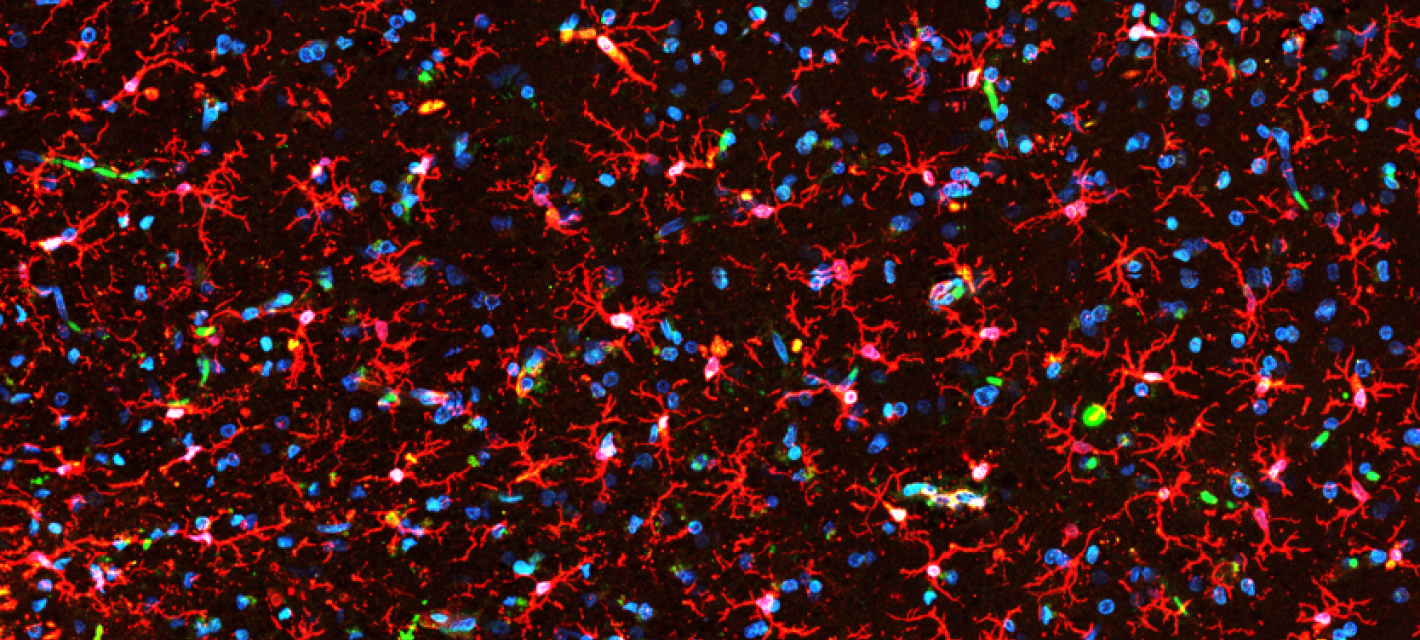

The Picower Institute is a community of scientists dedicated to understanding the mechanisms that drive learning and memory and related functions such as cognition, emotion, perception, behavior, and consciousness. Institute neuroscientists explore the brain and nervous system at multiple scales, from genes and molecules, to cells and synapses, to circuits and systems, producing novel insights into how disruptions in these mechanisms can lead to developmental, psychiatric or neurodegenerative disease.